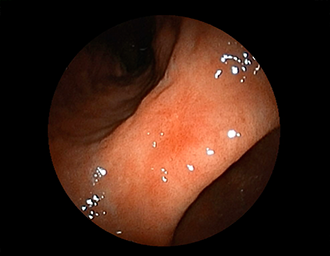

症例1:胃潰瘍(37才、男性)

①胃潰瘍(Stage A1)

健診:胃レントゲン検査で、胃角部ニッシェを指摘され当院受診。

胃角部小弯に、深くて大きな、大きさ約10mmの胃潰瘍(stage 1)

があり、潰瘍底は一部白苔はみ出しを認める。エソメプラゾールマグネシウム水和物投薬で治療開始しました。

(通常画像)